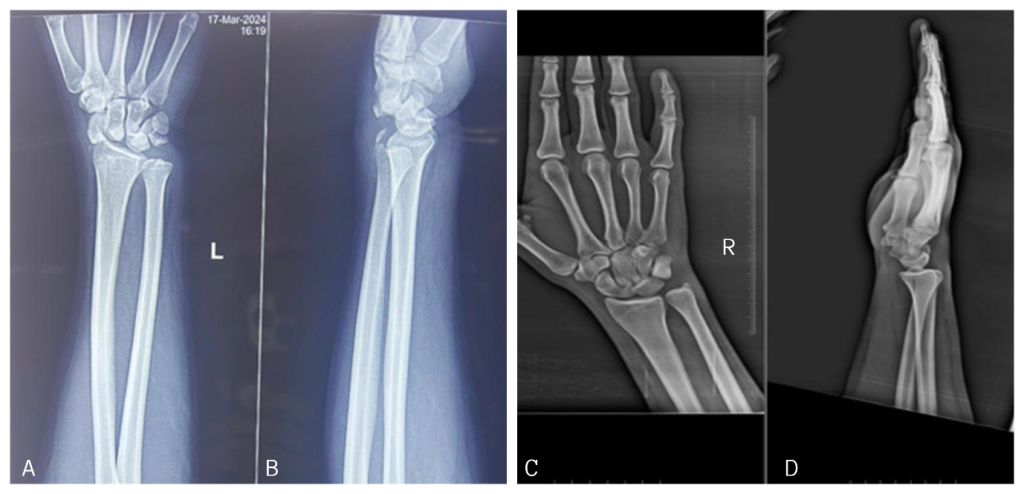

On examination, there was tenderness in the anatomical snuff box on both sides, and the scaphoid compression test was positive bilaterally. There was a significant restriction in the movements of both wrists. He was evaluated with X-rays (Fig. 1) and CT (Fig. 2) of the bilateral wrist and was diagnosed as a case of bilateral closed scaphoid fracture (Herbert type B4 on the left side and type B2 on the right side) with transcaphoid, trans-triquetrum perilunate dislocation on the left side and coronoid fracture (Regan-Moorey II) on the left side (Fig. 3). Closed reduction of perilunate dislocation was done in an emergency under local anesthesia, and a bilateral glass holding slab was applied for scaphoid fracture. While the patient had no prior comorbidities, bone health markers such as serum calcium and Vitamin D levels were evaluated and found to be within the normal range. The patient had no history of smoking or alcohol consumption. These may be important determinants of healing, particularly in older or systemically compromised individuals.

Figure 1: Pre-operative X-rays of the bilateral wrist. Anteroposterior (a) and lateral (b) view of the left wrist. Anteroposterior (c) and lateral (d) view of the right wrist.